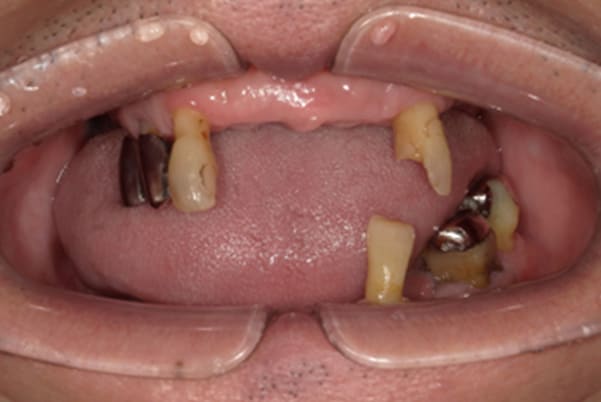

症例レポート[CASE.04]

前歯がとれて痛い、

食事もできず、見た目も悪い

- 女性(60代)

- 前歯がとれて、痛い、食事ができない、見た目が悪く人に会えないので何とかしてほしい

- 治療

-

- 上顎精密金属総入れ歯

- 下顎精密金属部分入れ歯

- 磁性アタッチメント(白金加金) 1歯

上前歯はブリッジの差し歯により根が折れ炎症を起こしお痛みのある状態でした。

原因は長期使用により下の義歯の歯が削れたことにより、下前歯が上前歯を突き上げ強い力が加わっていたことが根本的な原因と考えられます。

治療前は、奥歯が下がり、かみ合わせが乱れています。適切な入れ歯はそのままのかみ合わせで義歯を作るのではなく治療後のように、前歯から奥歯までのラインが真っすぐ揃った、かみ合わせの面を適切に付与し、よく咬め、残りの歯に負担がかからないかみ合わせとしました。

とにかく何も食べられないこと、人に会えないことから、なるべく早く何とかしたいとのご希望でした。

患者様とご相談の上、まず早急に上記を回復させるため、初診含め3度の来院でお食事ができ、見た目を回復できるように治療用義歯を作製、装着しました。

本来は、数本の上前歯の折れてしまって残せない歯は抜いてから歯肉の治癒を待ち、数か月後に型どりから作製になりますが、抜歯即時義歯といって、歯を抜く前に型、かみ合わせをとり、抜歯を行ったその日に上下の義歯を装着する特殊な治療法を用いたことで、10日後には治療用義歯をお口に装着することができ、お痛みもなくお食事ができ、ご友人とのお食事にも行けることが可能になりました。

本来、入れ歯作製は技工所と言って、義歯を作製する所に発送するため、作製には時間がかかりますが、院内に技工専用スペースを完備しており、長年、義歯治療において、技工も技術の習得してきましたので技工士さんではなく、かみ合わせの道具も私自身で院内で作製したことで、初診日の次の日にご来院いただきかみ合わせを採ることで、診断、型どり、かみ合わせ、装着まで10日という最短のご希望にこたえらた方です。

上顎治療前

上顎治療後

根のみの7本は虫歯にもなっており歯肉は腫れあがっています。

残りの歯もレントゲンで重度の歯周炎によりぐらぐらな状態でした。